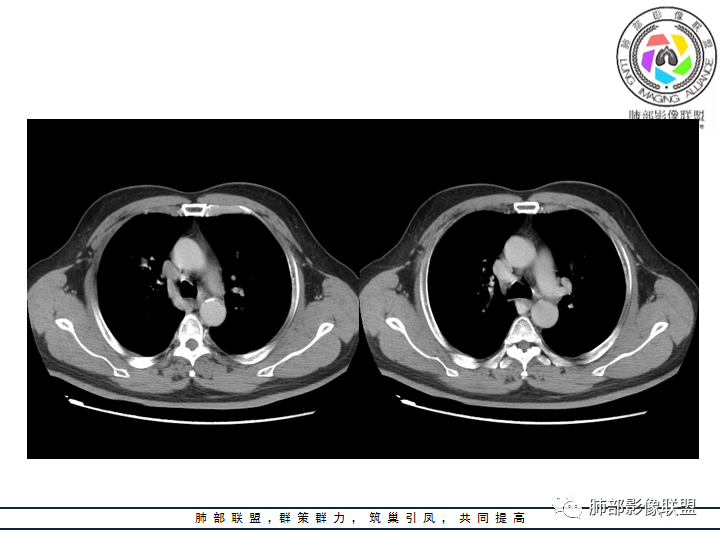

老年男性患者,长期吸烟史,没有呼吸系统临床表现。胸部CT示右肺上叶实性密度结节影,密度均匀,未见空洞及钙化,边缘较光整,未见分叶及毛刺。血管影旁现侧出,支气管进入并截断,不均匀强化。

影像上结节影或块影一旦与支气管密切相关(如截断),不支持硬化性肺细胞瘤、错构瘤、孤立性纤维瘤等良性病灶。如此清晰的边缘也不符合一般意义上的炎性渗出。

——本例鳞癌病理意见可以符合,只是太光整、太干净,且病灶不大,未能显示出坏死等特征,我们从影像上难以得出倾向性意见。

恶性病灶需要排除的有神经内分泌癌(大细胞癌、小细胞癌、类癌)、鳞癌、淋巴瘤样上皮癌、淋巴瘤等等。